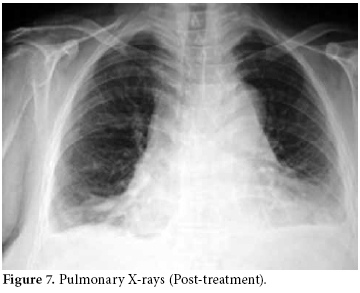

The pericardiocentesis fluid and blood cultures were negative, and the control ECHO was normal in the third and fifth days. The effusion had completely disappeared. Therefore, taking into account all clinical, radiological, and laboratory findings, the patient was diagnosed with DILE due to the use of sulphasalazine. Existing minimal pleural effusion was reported by the pulmonary disease department (figure 7). Liver enzyme and ferritin levels were normal. The other laboratory changes before discharge were as follows: leukocyte count: 18800/mL, Hgb: 12.7 g/dl, CRP: 3.84 mg/L, RF: 37 IU/mL (0-15), ESR: 22 mm/hour, anti-CCP: positive, ANA: negative, anti-histone antibodies: positive, and anti-dsDNA: negative. Urine analysis findings were within normal limits, and the DAS was calculated as 3.06.